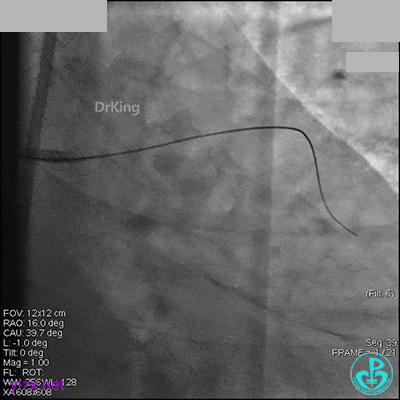

AL 1.0指引导管到位,简单短时尝试导丝不能顺利通过前降支或回旋支病变。改变策略处理右冠脉病变,计划植入2枚支架。AL指引导管到位,Sion blue导丝到达右冠脉远端。导丝通过后1.5mm及2.5mm球囊14~16atm充分扩张中段病变。